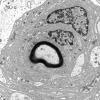

1J4A Massive Onion Bulbs (Case 1) Plastic 40X1

1J4B Massive Onion Bulbs (Case 1) Plastic 40X2

1J4C Massive Onion Bulbs (Case 1) Plastic 100X 1

1J5 Massive Onion Bulbs (Case 1) Plastic 40X scale 40X 1